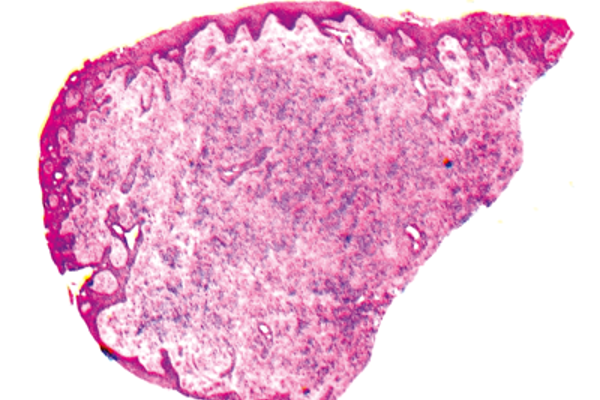

Pathology Quiz - Section Editor until Aug/Sep 2016